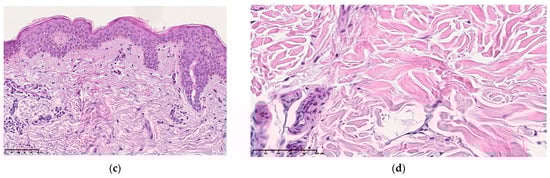

Microscopy of skin sections of patients with normal aging visualizes the preservation of its architectonic structure. In the basal layer of the epidermis, epithelial cells are prismatic in shape with well-defined boundaries, their nuclei are visualized in the basal part. Some cells are in the stage of mitotic division. The cells of the spinous layer are large in size, the shape of the nuclei is close to spherical, arranged in several rows. The cells of the granular layer have a flattened shape, and dark strong granules of keratogyalin are visualized in their cytoplasm (Figure 4a,b).

Micrography of the skin section in the comparison group is an intact skin area of patients with normal skin aging: (a,b) stained with hematoxylin and eosin, (c,d) stained according to the Mallory method, (e,f) stained according to the Van Gieson method. ×100 (a,e), ×200 (b–d,f).

The dermis is formed by papillary and reticular layers. The border between the epidermis and the dermis is smoothed, the epidermal papillae are short and wide. The papillary layer of the dermis is formed by loose fibrous connective tissue, the fibrous component of which is formed by fibers arranged randomly and disordered, without a tendency to form bundles. Connective tissue fibers are thin, and the degree of their heterogeneity is poorly expressed. The cellular component is heterogeneous in its composition. The border between the papillary and reticular layers is moderately pronounced; there is a smooth transition of one type of connective tissue to another (Figure 4c,d). The reticular layer is formed by dense irregular connective tissue. Bundles of collagen fibers oriented in different directions are visualized in its thickness. The fibrous component prevails over the cellular one (the structured substance of the dermis of the skin). Inter-fiber spaces (unstructured matter) are visualized between bundles of connective tissue fibers (Figure 4d,e).